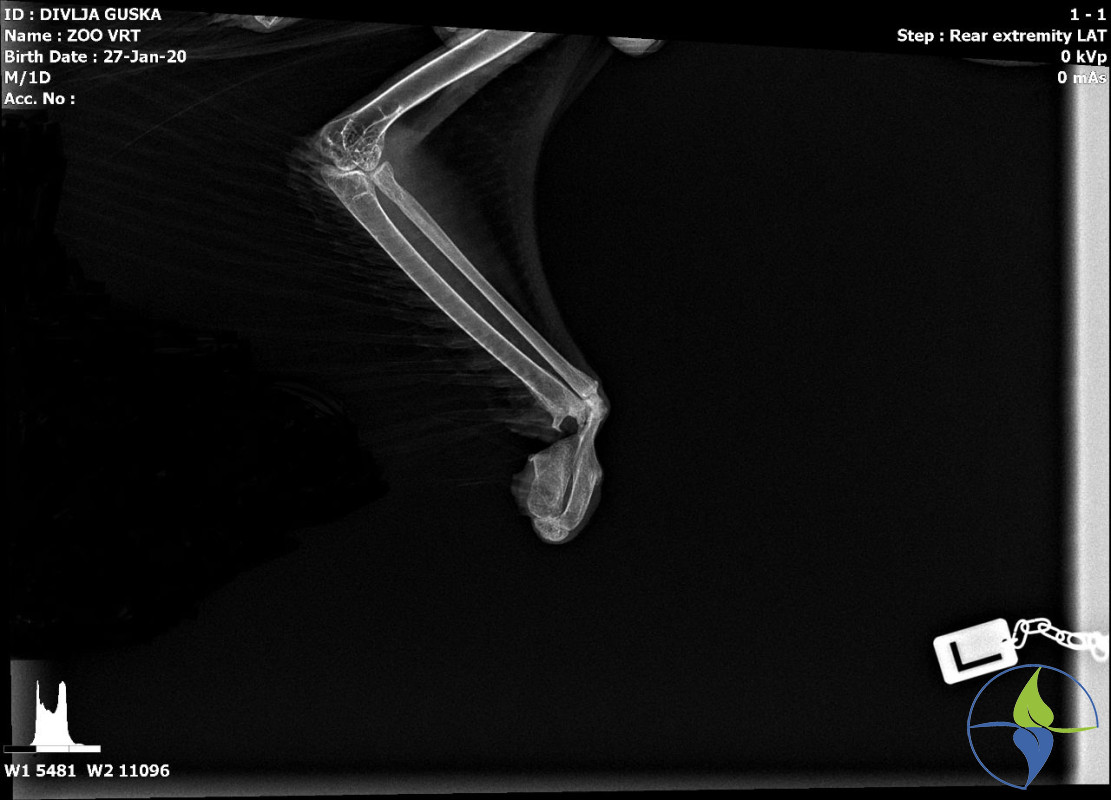

Novi Sad, 3.2.2020. - Dana 26. januara 2020. Pokrajinska inspekcija za zaštitu životne sredine, u saradnji sa Pokrajinskim zavodom za zaštitu prirode, oduzela je od Ž. T. (63) iz Bačkog Gradišta dve divlje guske (Anser anser) koje je ova osoba nudila na prodaju na berzi sitnih životinja koja je organizovana tokom trajanja Sajma peradarstva u Somboru. Po sopstvenom iskazu, Ž. T. je ove životinje dobio kao male ptice dok su još bile u paperju, a vremenom ih je zadržao, hranio i amputirao im krila. Obe jedinke su, zbog prekršaja Zakona o zaštiti prirode, koji zabranjuje držanje u zarobljeništvu i prodaju strogo zaštićenih divljih životinja, privremeno oduzete i smeštene na oporavak u Prihvatilište za divlje životinje Zoo vrta na Paliću. Po pristizanju u Prihvatilište, veterinar ih je pregledao i snimio rentgenom, utvrdivši da obe divlje guske imaju amputirano levo krilo, te da je krilo presečeno na sredini kostiju krila. Protiv Ž. T. biće podneta prijava pravosudnim organima za držanje u zarobljeništvu i nuđenje na prodaju strogo zaštićene vrste, a ptice će ostati u prihvatilištu, budući da su trajno onesposobljene za let.